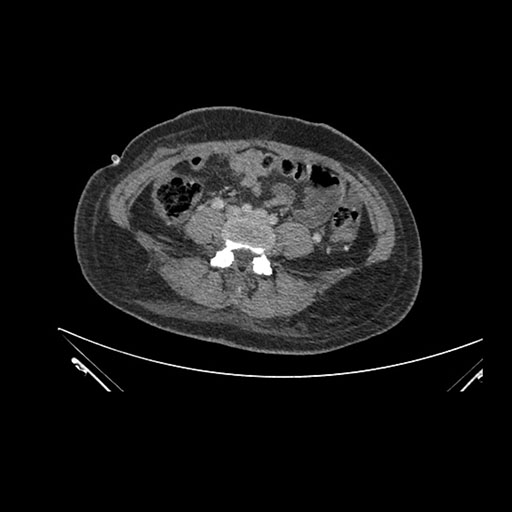

Axial Arterial